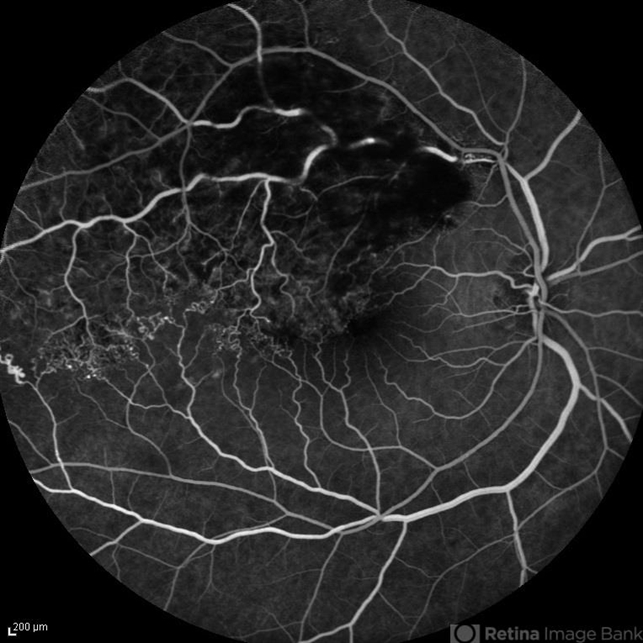

- FA image of the right eye of a 60-year-old man with recurrent BRVO. Multiple collaterals are visible secondary to previous BRVO.